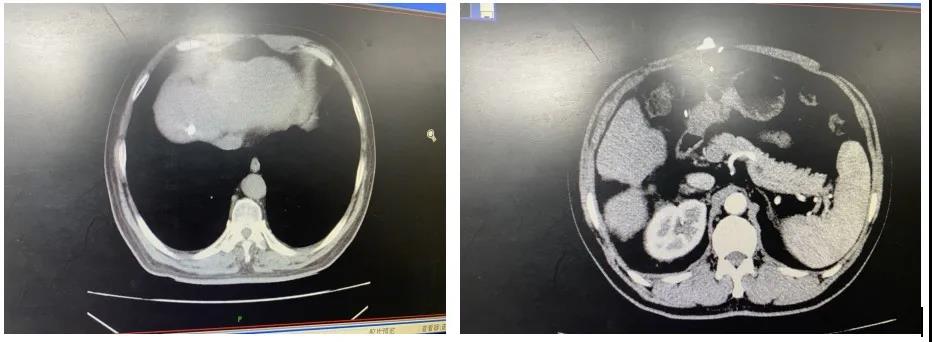

2020年5月11日患者出现乏力,纳差。复查CT发现:右下肺微结节;肝硬化、脾大;右肾高密度囊肿表现;肝右叶异常强化灶,新发转移病灶(图4),提示局部进展。局部采取TACE治疗,继续口服瑞戈非尼。2020年6月6日复查CT(图5):右下肺微结节未见明显改变;肝硬化、脾大;右肾高密度囊肿表现;肝右叶顶部新增病灶治疗后碘油栓塞良好,病灶控制,余复查稳定。继续口服瑞戈非尼控制病情。八月份复查MRI,病灶稳定,体力良好。继续口服瑞戈非尼治疗。